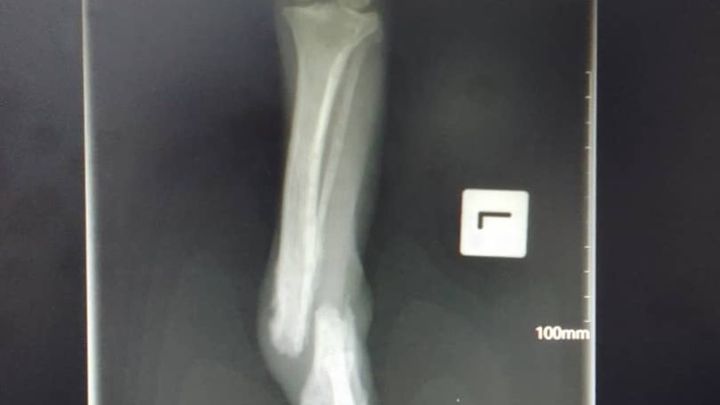

Hi, I am one of the vets at the RSPCA PNG and I am helping to fundraise for a new xray machine as ours broke recently. Unfortunately, dogs getting run over by cars is a daily occurrence here in Papua New Guinea. If we are lucky we can fix a fracture, or even amputate a leg but still save an animal's life. Other times the injuries are so severe that humane euthanasia is the kindest thing to do. Not having an xray machine is like flying blind and a lot of animals that could be saved are put to sleep or go through unnecessary suffering as we can make the wrong choice. You can help prevent this by helping us fundraise for an xray machine.